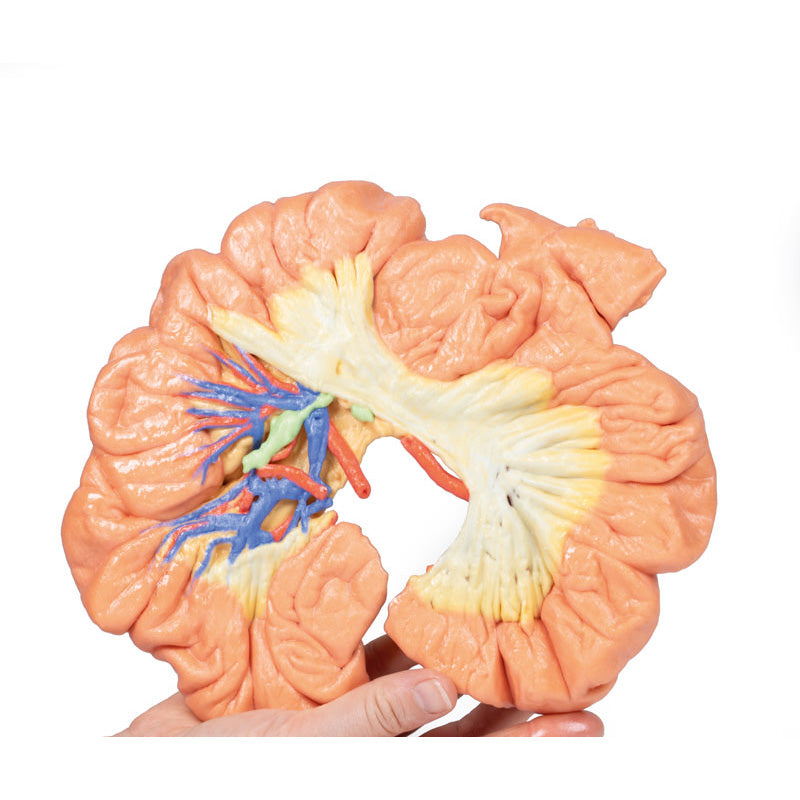

There are several large lymph nodes surrounding the larger vessels near the root of the mesentery. A distinct feature of the fat in the mesentery extending up to (and indeed, beyond) the mesenteric border of the bowel.

A small portion of the lumen has been opened to reveal the nature of the mucosal folding (fewer but larger folds than jejenum).

This 3D printed specimen demonstrates a small loop of ileum and mesentery. A window into the mesentery has been dissected (removing fat and visceral peritoneum) to show arterial arcades in the mesentery (many short vasa rectae and more numerous arcades than in jejenum).There are several large lymph nodes surrounding the larger vessels near the root of the mesentery. A distinct feature of the fat in the mesentery extending up to (and indeed, beyond) the mesenteric border of the bowel.

A small portion of the lumen has been opened to reveal the nature of the mucosal folding (fewer but larger folds than jejenum).